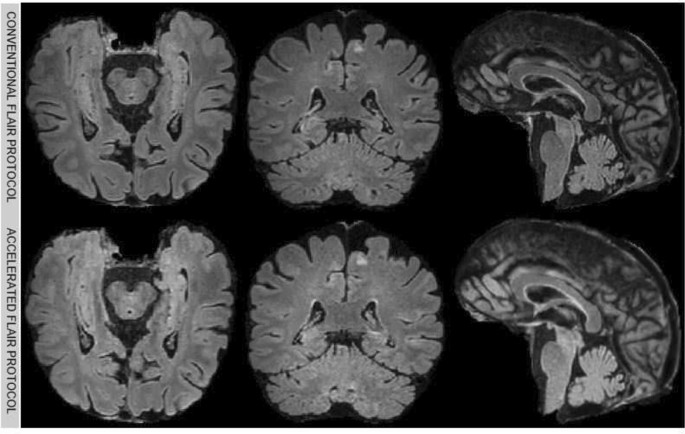

Figure 1 compares standard and accelerated T1w images of the same patient, highlighting subtle differences in brain tissue definition and anatomical boundaries. In Fig. 2 standard and accelerated T2-FLAIR sequences are presented.

T1w skull-stripped images of conventional (top) and accelerated (bottom) protocols. In each row the axial, coronal, and sagittal planes are shown from left to right.

T2-FLAIR skull-stripped images of conventional (top) and accelerated (bottom) protocols. In each row the axial, coronal, and sagittal planes are shown from left to right.